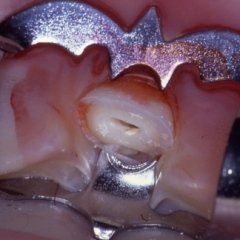

P3: Il trattamento endodontico si rende necessario quando la polpa del dente, comunemente chiamata dai Pazienti “nervo” è stata irrimediabilmente danneggiata da carie penetranti, fratture dentali, traumi o da cause imputabili a pratiche odontoiatriche scorrette. A volte la devitalizzazione del dente si rende necessaria, in corso di riabilitazioni protesiche complesse, per prevenire possibili problemi di ipersensibilità o per poter coinvolgere nel progetto terapeutico di recupero denti già di per se compromessi dal punto di vista parodontale. Presupposto per ottenere il successo in tale terapia è l’applicazione di un serio protocollo operativo che prevede tra l’altro l’uso di un telo di lattice, chiamato comunemente “diga”, che consenta la detersione e la pulizia dei canali del dente in un ambiente sterile e il controllo delle diverse fasi del trattamento attraverso delle radiografie endorali.